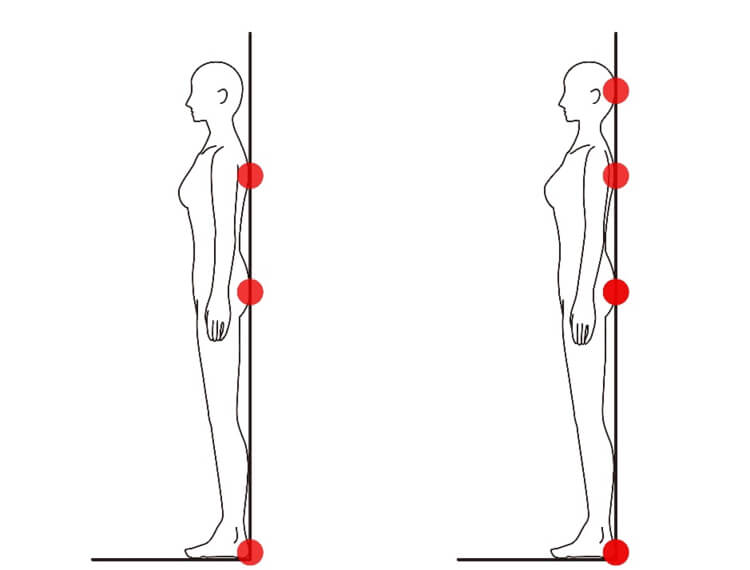

「正しい姿勢の習得」は頚椎症性脊髄症の患者様にとって、非常に重要なステップとなります。日常生活での繰り返しの悪い姿勢が、この症状の主な原因となっているからです。

適切な姿勢の習得を助けるために、壁や鏡を利用して姿勢を確認しながらのトレーニングや、筋力を強化するリハビリが推奨されます。首への負担を最小限にすることで、症状の進行を遅らせる効果が期待できます。